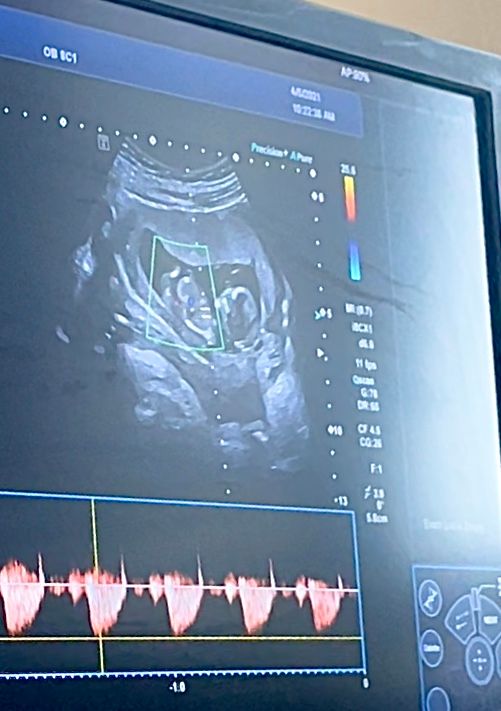

Первый скрининг 🤰🏽

Срок по УЗИ 12+6, по М 11+6

ПЯ 59 мм (13 нед.)

КТР 64 (12+6 нед.)

БПР 21,1 (13+3 нед.)

ЛЗР 28 мм (12+1 нед.)

Носовые косточки лоцируются нечетко 4,6-4,7 мм

ТВП 2.0 мм

ЧСС 158 уд/мин

Плацента 18 мм, на правой заднем-боковой стенки матки, 0 ст. зрелости.

Длина шейки 31 мм. Зев сомкнут, цервикальный канал не расширен.

Двигательная активность удовлетворительная